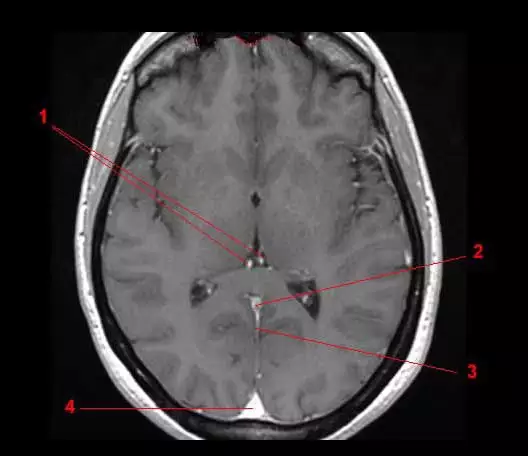

图8 颈内静脉和椎静脉(磁共振断面)

1.大脑内静脉;2.大脑大静脉;3.直窦;4.上矢状窦。